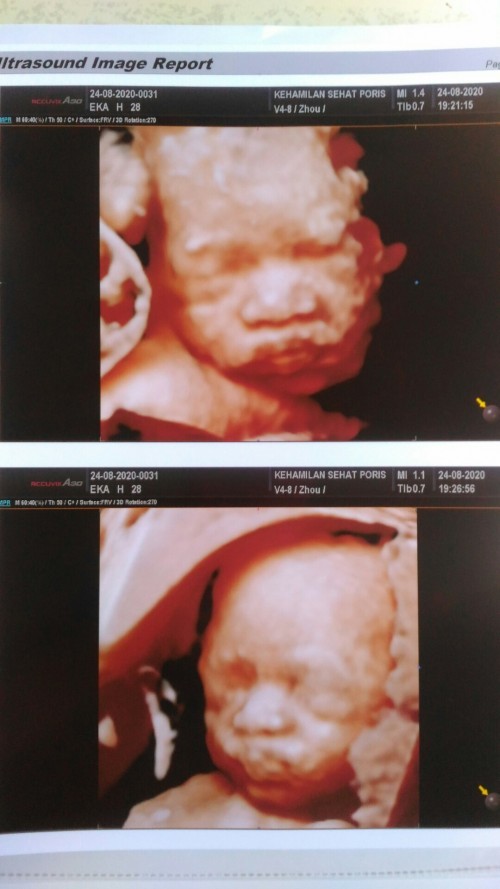

Nih Bun,. Pipinya menggemaskan sampe sekarang pun udah jalan 6 bulan 😊

Itu pas 28 week Bun.. dokternya jg gemes sama pipinya 😁